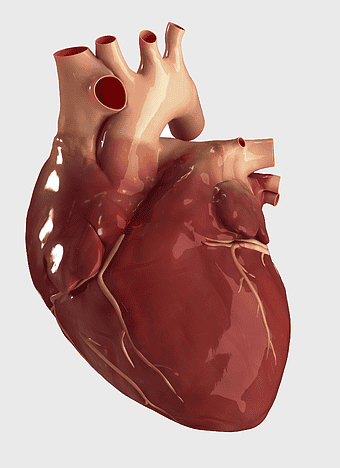

- heart and lung anatomy

red heart anatomy, human heart drawing, cartoon heart illustration, love and biology, cardiovascular system diagram, medical art depiction, organ structure visualization -

human heart diagram, monochrome anatomy drawing, black and white heart illustration, human organ sketch, cardiovascular system diagram, medical illustration heart, heart structure outline -

Heart Anatomy Diagram, human heart drawing, realistic heart illustration, cardiovascular system, medical illustration, organ structure, human anatomy study -

human heart anatomy, cardiovascular system illustration, medical heart diagram, heart organ structure, human body organ visuals, anatomical heart drawing, heart health -

human heart diagram, cardiovascular system anatomy, blood vessel chart, free body diagram, circulatory system illustration, medical organ visualization, human anatomy study -

human heart anatomy, cardiac muscle illustration, circulatory system model, heart health visual, cardiovascular organ diagram, medical heart image, visceral structure depiction -

human heart anatomy, red heart illustration, heart organ diagram, heart muscles and valves, cardiovascular system diagram, human body organ chart, anatomical heart structure -

human heart anatomy, superior vena cava illustration, systemic circulation diagram, heart rate visual, cardiovascular system study, medical organ depiction, human body organ reference -

heart anatomy diagram, human heart ventricle, human body physiology, heart beat animation, cardiovascular system, medical illustration, organ structure analysis -

human heart illustration, cardiac anatomy diagram, heart blood vessels, medical organ visuals, cardiovascular system chart, human anatomy study, circulatory system illustration -

human heart anatomy illustration, watercolor heart painting, heart shape medical care, red heart organ, cardiovascular system diagram, anatomical heart drawing, heart structure analysis -

human heart anatomy, heart science illustration, human body heart diagram, cardiovascular system, cardiac structure, medical heart image, heart health education -

heart anatomy illustration, cardiovascular system diagram, circulatory system medical, vascular system sonography, human body blood flow, arterial network visualization, heart function analysis -

human heart drawing, red line art heart, anatomical heart illustration, heart organ diagram, cardiovascular system sketch, medical heart graphic, heart anatomy chart -

heart anatomy diagram, circulatory system illustration, superior vena cava label, inferior vena cava structure, cardiovascular system chart, human heart ventricles, medical education graphics -

human heart anatomy, American Heart Association drawing, red blood vessel illustration, fictional character heart, cardiovascular system diagram, medical art illustration, organ structure depiction -